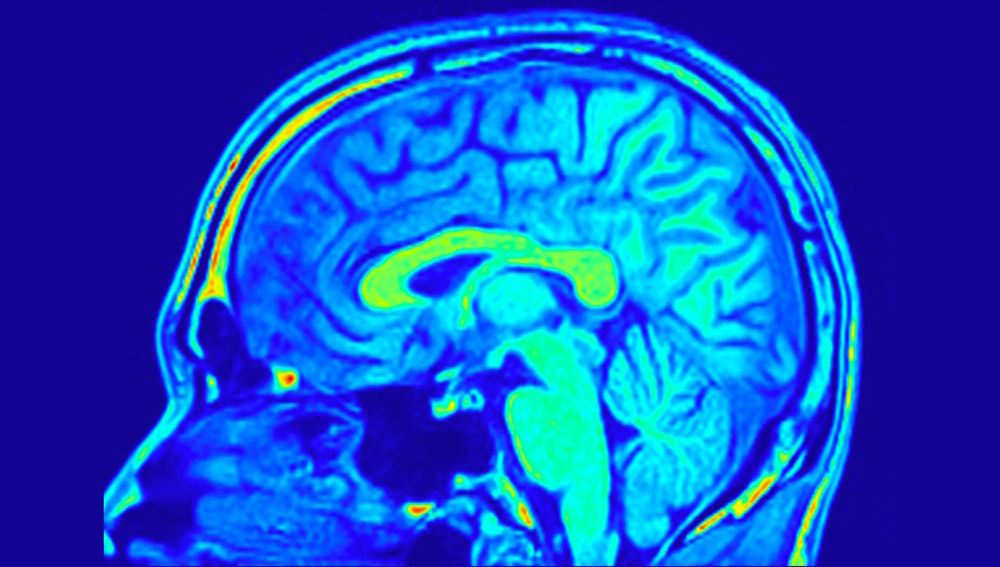

МРТ показала, как работает мозг чемпиона США по запоминанию

Такой подход активировал те же три кортикальные области, но изменил активность в гиппокампе — изогнутой структуре глубоко внутри мозга, играющей ключевую роль в памяти. В первом задании активность гиппокампа была выше во время кодирования (то есть приема новой информации и связывания ее с уже известной), чем во время воспоминания. Во втором картина сменилась на противоположную. Кроме того, в задании с картами активировались хвостатые ядра — С-образные структуры, участвующие не только в памяти, но и в обучении. Исследователи предположили, что вовлечение хвостатых ядер превращает память в «устойчивый навык».

Активность мозга рекордсмена сравнили с данными 887 участников проекта Human Connectome Project. Оказалось, что у него гораздо выше показатель функциональной связности — то есть разные области его мозга координируют свою работу более эффективно, что говорит об их слаженном взаимодействии.